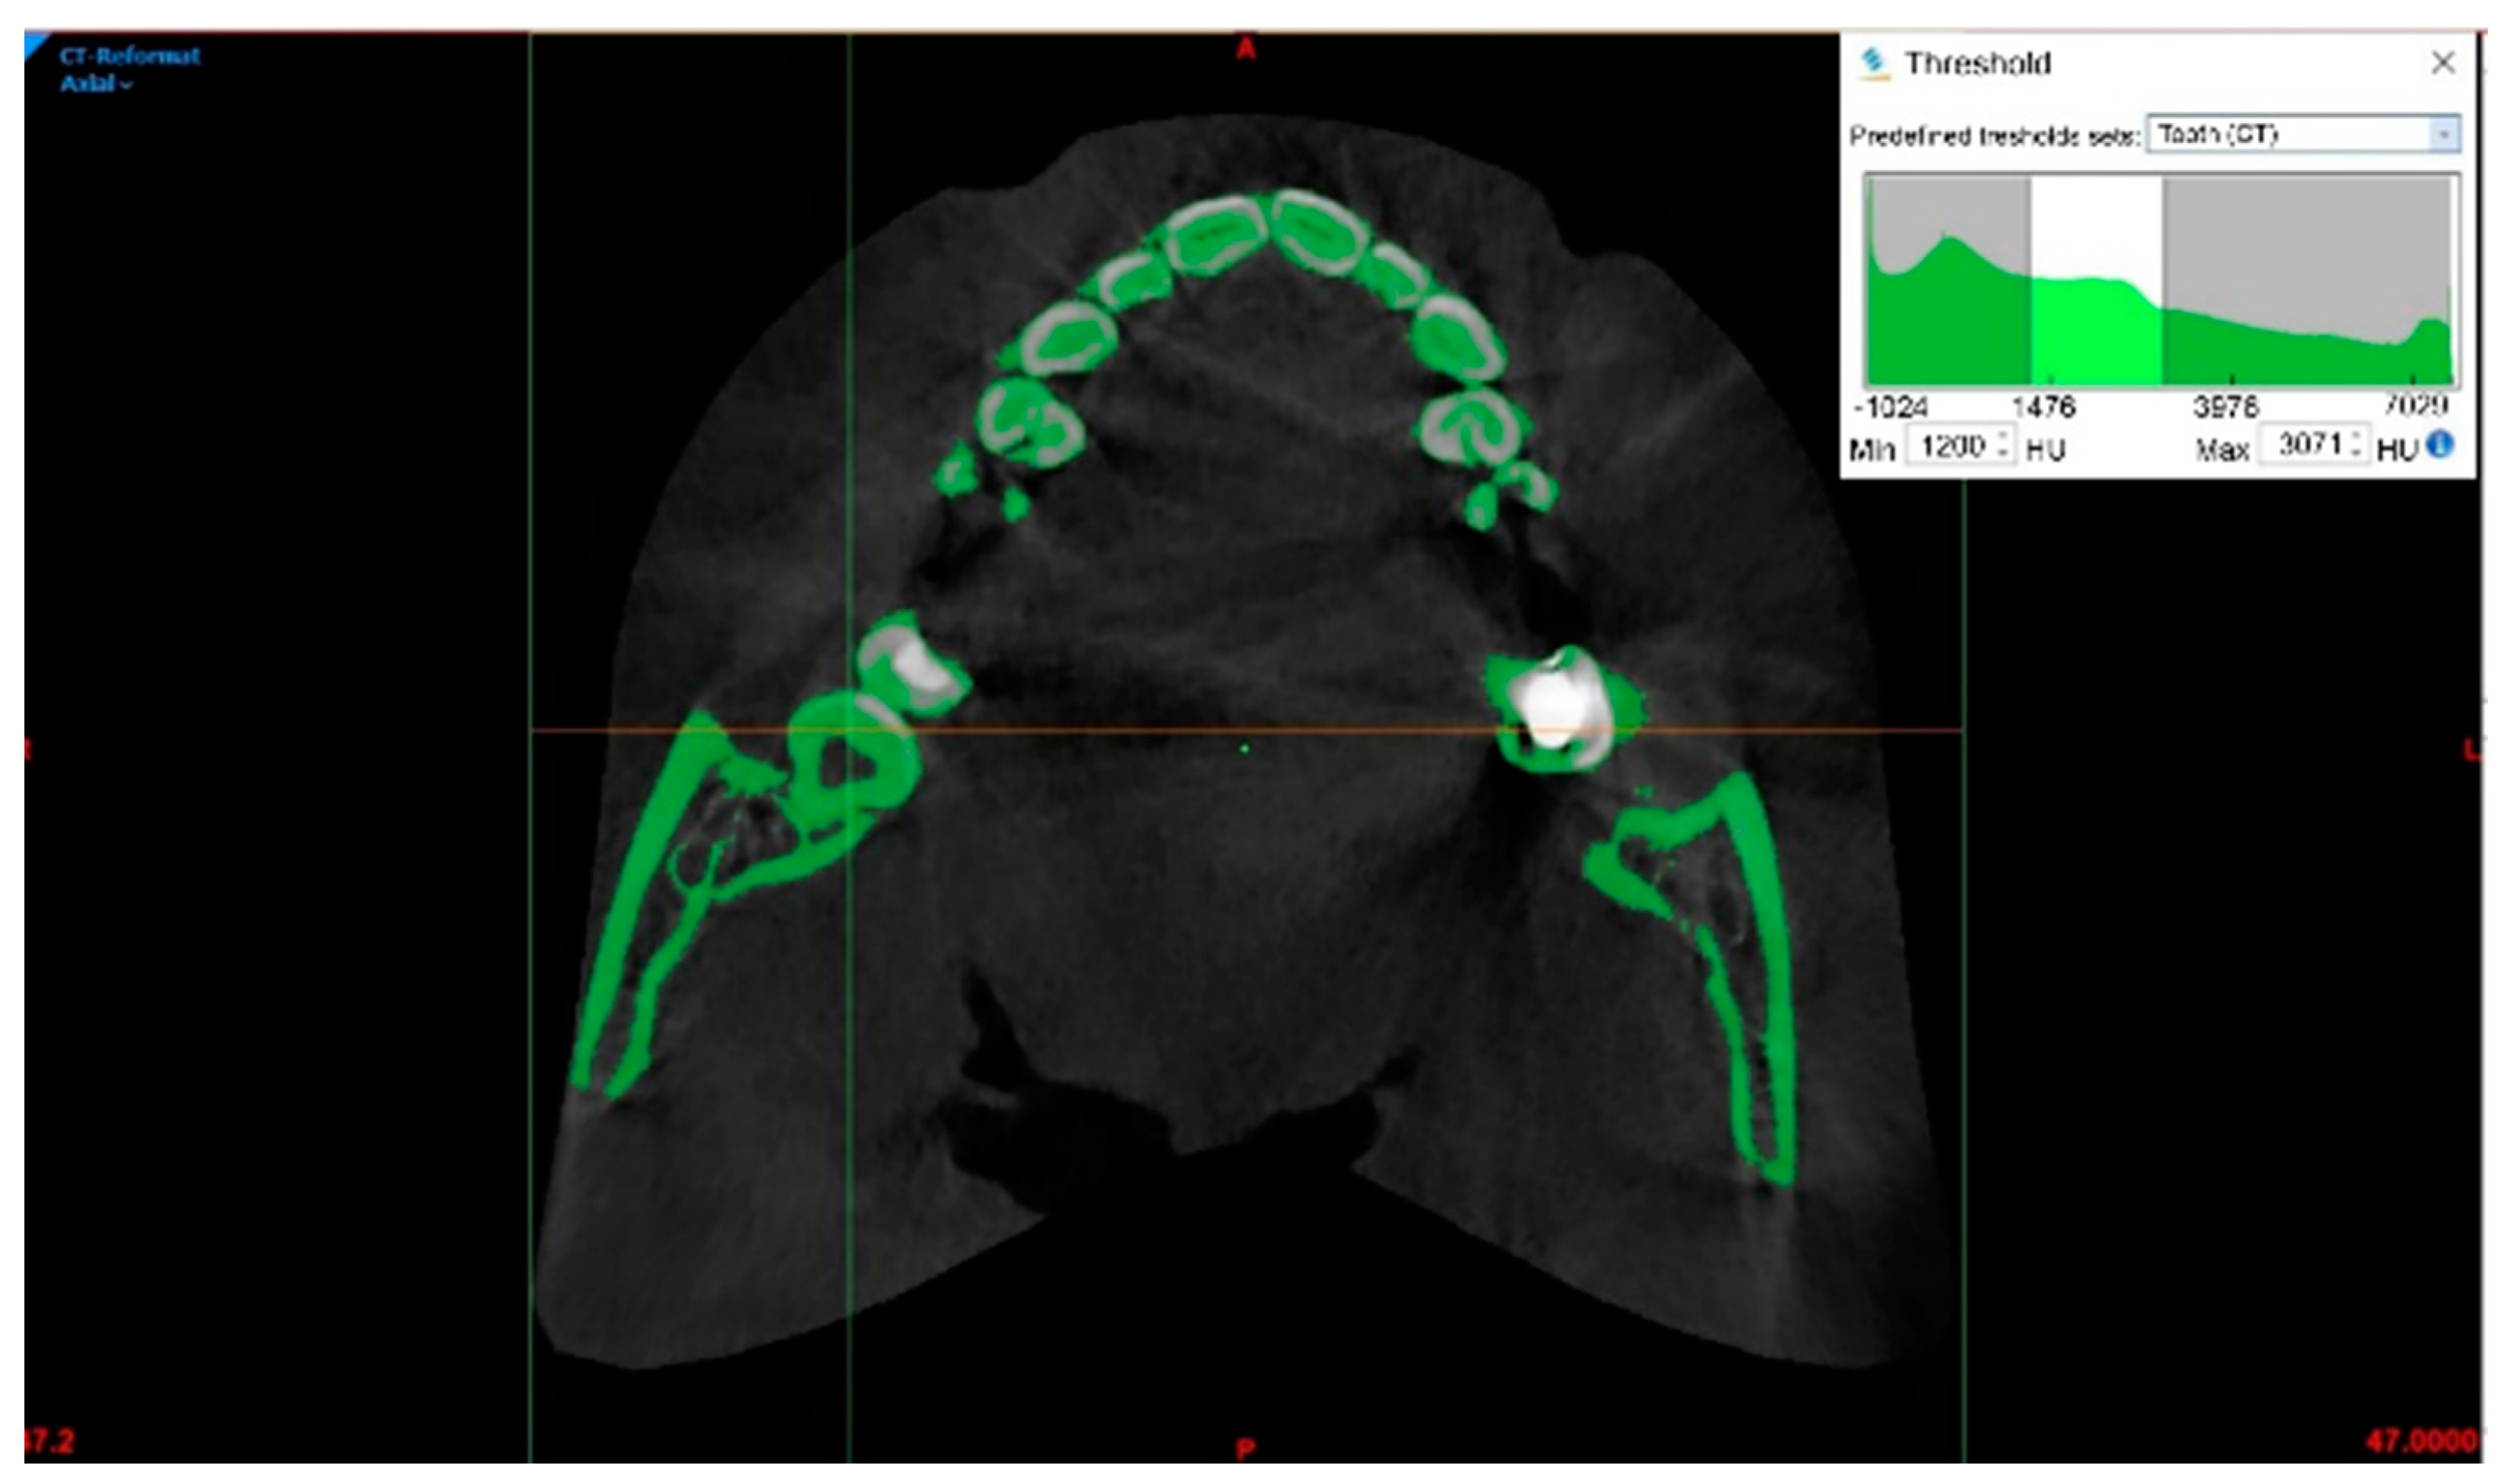

A cone beam computed tomography (CBCT) scan (0.4 mm) of the upper and lower jaw was obtained. The scanned data were imported into Mimics software (V21; Materialise; Leuven, Belgium) in DICOM format. Three main planes—axial, sagittal, and coronal—were used to display CBCT scans. To segment a certain tooth, the dental tissue selection needs to be defined using the Threshold function, which corresponds to various shades of gray in HU (Figure 1). To simplify the segmentation, the area of interest (lower right wisdom tooth) can be de-limited. Different HU ranges are also defined for the teeth under the Threshold function (tooth (CBCT); min = 1200 HU, max = 3071 HU).

Figure 1. Definition of the threshold donor tooth shown by the arrow.